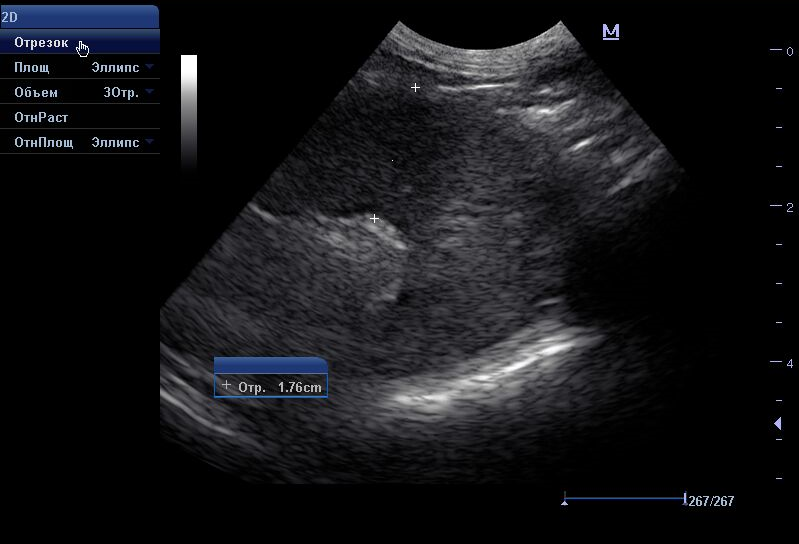

Рис. 3. Цитологическая картина лимфомы.